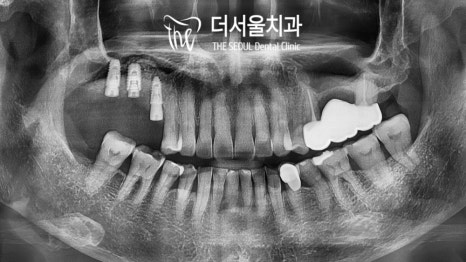

【 체계적이고 확실한 검진 】

좋은 결과를 얻기 위한 계획을 세우기 위해선

체계적이고 확실한 검진이 필수적인데요.

성남치과에서는 컴퓨터 분석을 사용하여

보다 안정적이고 확실한 계획을 세웠습니다.

【 상악동 거상술을 동반한 식립 】

임플란트 축농증 이 나타나지 않도록

성남치과에서는 상악동 거상술 및 골이식을

동반하여 수술을 진행했습니다.

아래로 내려와 있는 막을 들어 올려준 뒤

빈 공간을 이식재로 빼곡히 채워 넣었는데요.

이후 골 유착이 될 수 있도록 기간을 부여한 뒤

순차적인 식립을 도와드렸습니다.